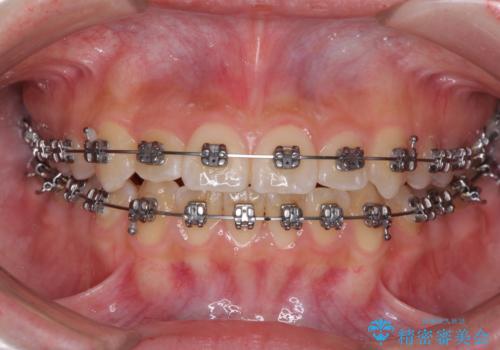

前歯のクロスバイト メタル装置での矯正治療

- メタルブラケット

前歯の叢生を解消するスペースを獲得するために上顎左右の親知らずを抜歯し、メタルブラケットにて矯正治療を行うこととしました。

当初は1年半程度の治療期間を想定していましたが、上下の正中を合わせていく過程で奥歯の咬みにくさが続いてしまい、2年以上の治療期間を要することとなりました。